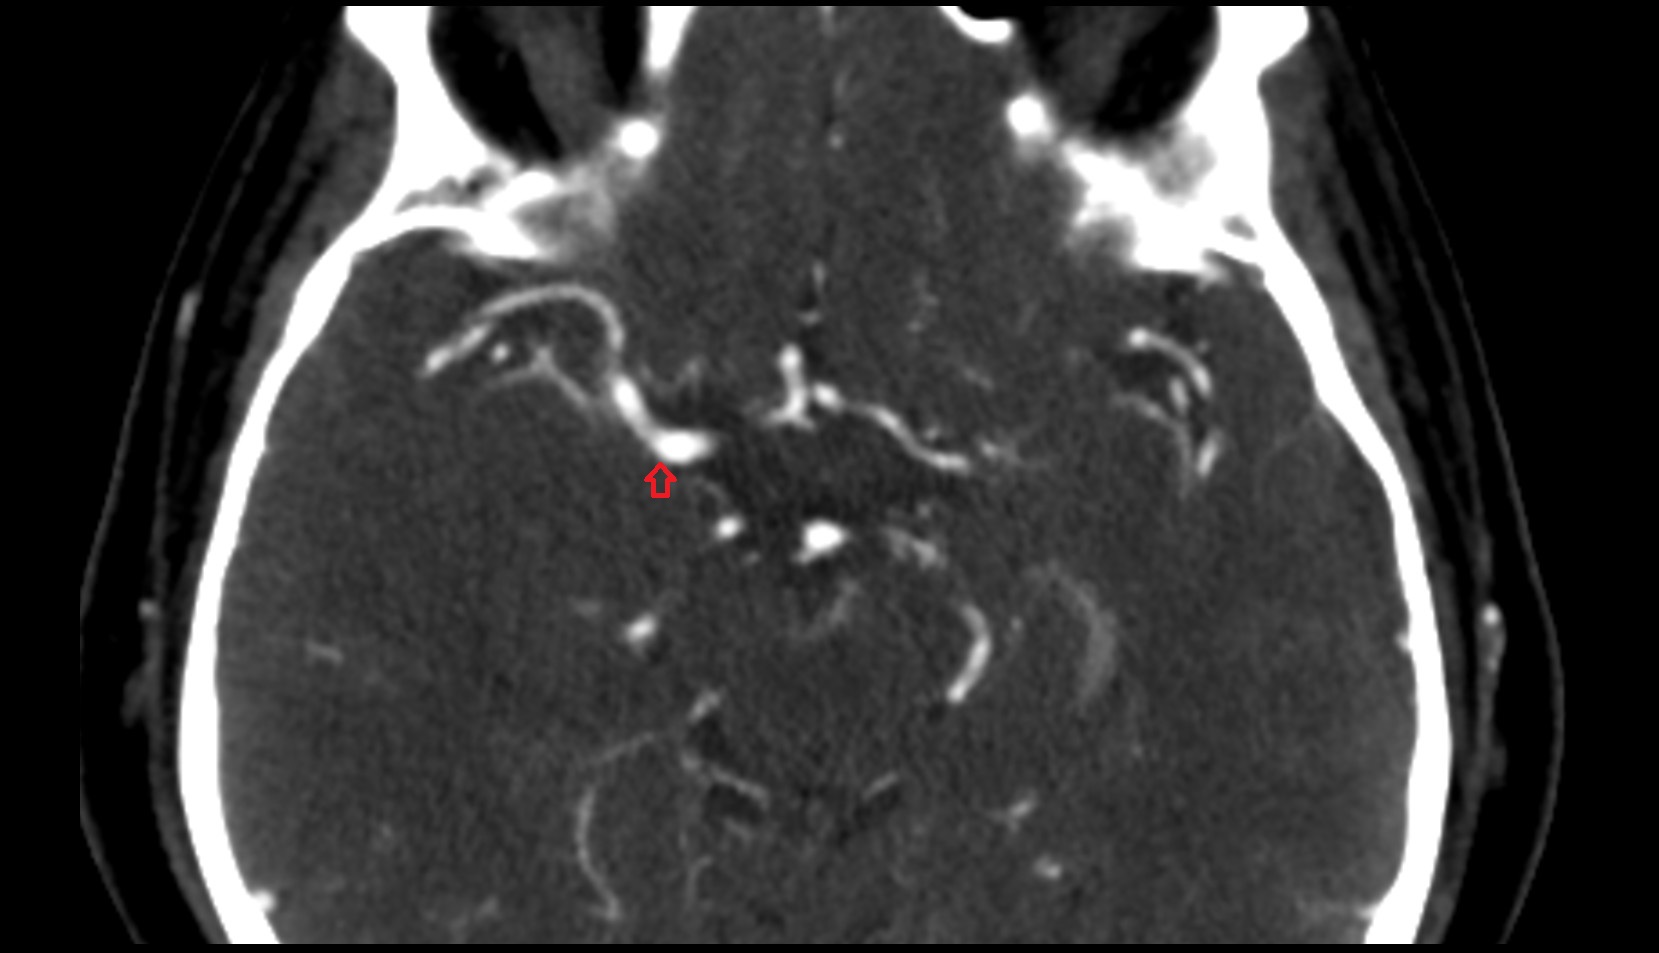

- Middle cerebral artery horizontal segment (M1)

- Middle cerebral artery insular segment (M2)

- Middle cerebral artery opercular segment (M3)

- Middle cerebral artery cortical segment (M4)